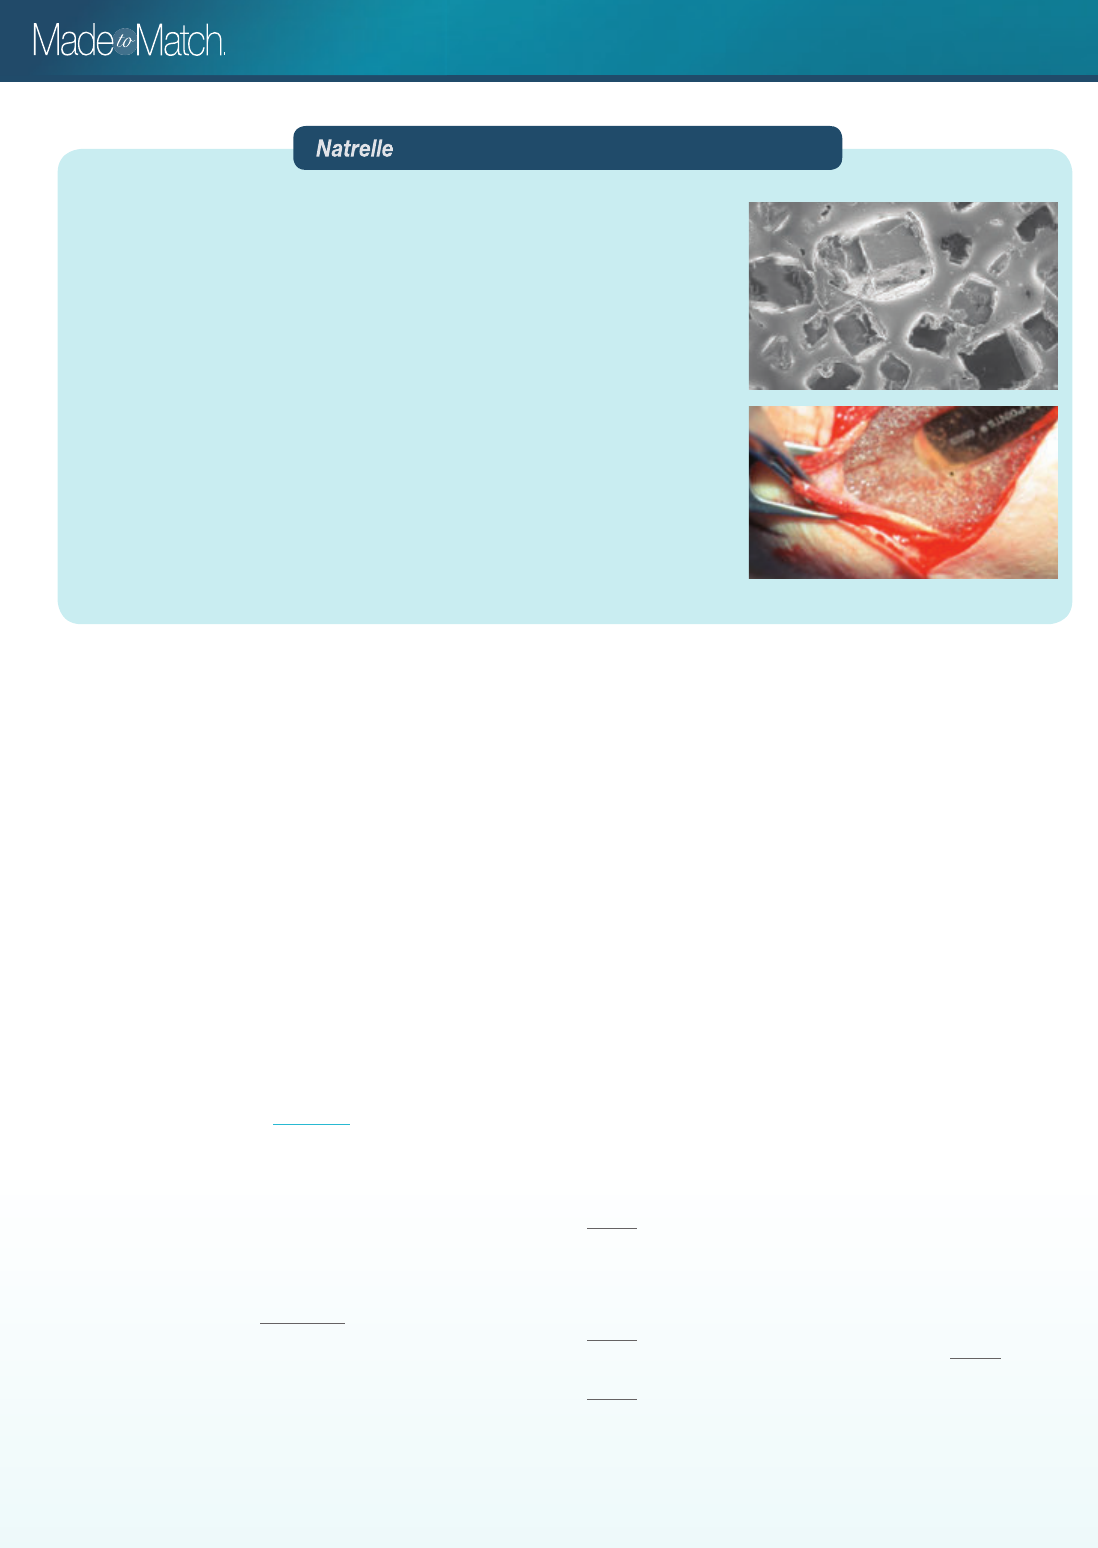

The BIOCELL® shell covering the Style 133

irregularly spaced cuboid wells.10 BIOCELL® is

The cuboid depressions of the textured surface

vary in size from 200 µm to 500 µm wide and

100 µm to 200 µm deep.11

When viewed by electron microscopy, the

surface of the capsule is a mirror image of the

textured surface of the device.12

BIOCELL® textured surface facilitates tissue

expander adherence to the surrounding

tissue,11-13 as fi rst demonstrated in Maxwell’s

landmark study on breast reconstruction with

BIOCELL® textured surface, integrated-valve,

anatomical tissue expanders.

Functionally, adherence of the BIOCELL®

textured surface to the periprosthetic breast

capsule promotes immobility of the expander.14

Tissue adherence at 4 months

Photo provided by Dr G. Patrick Maxwell.